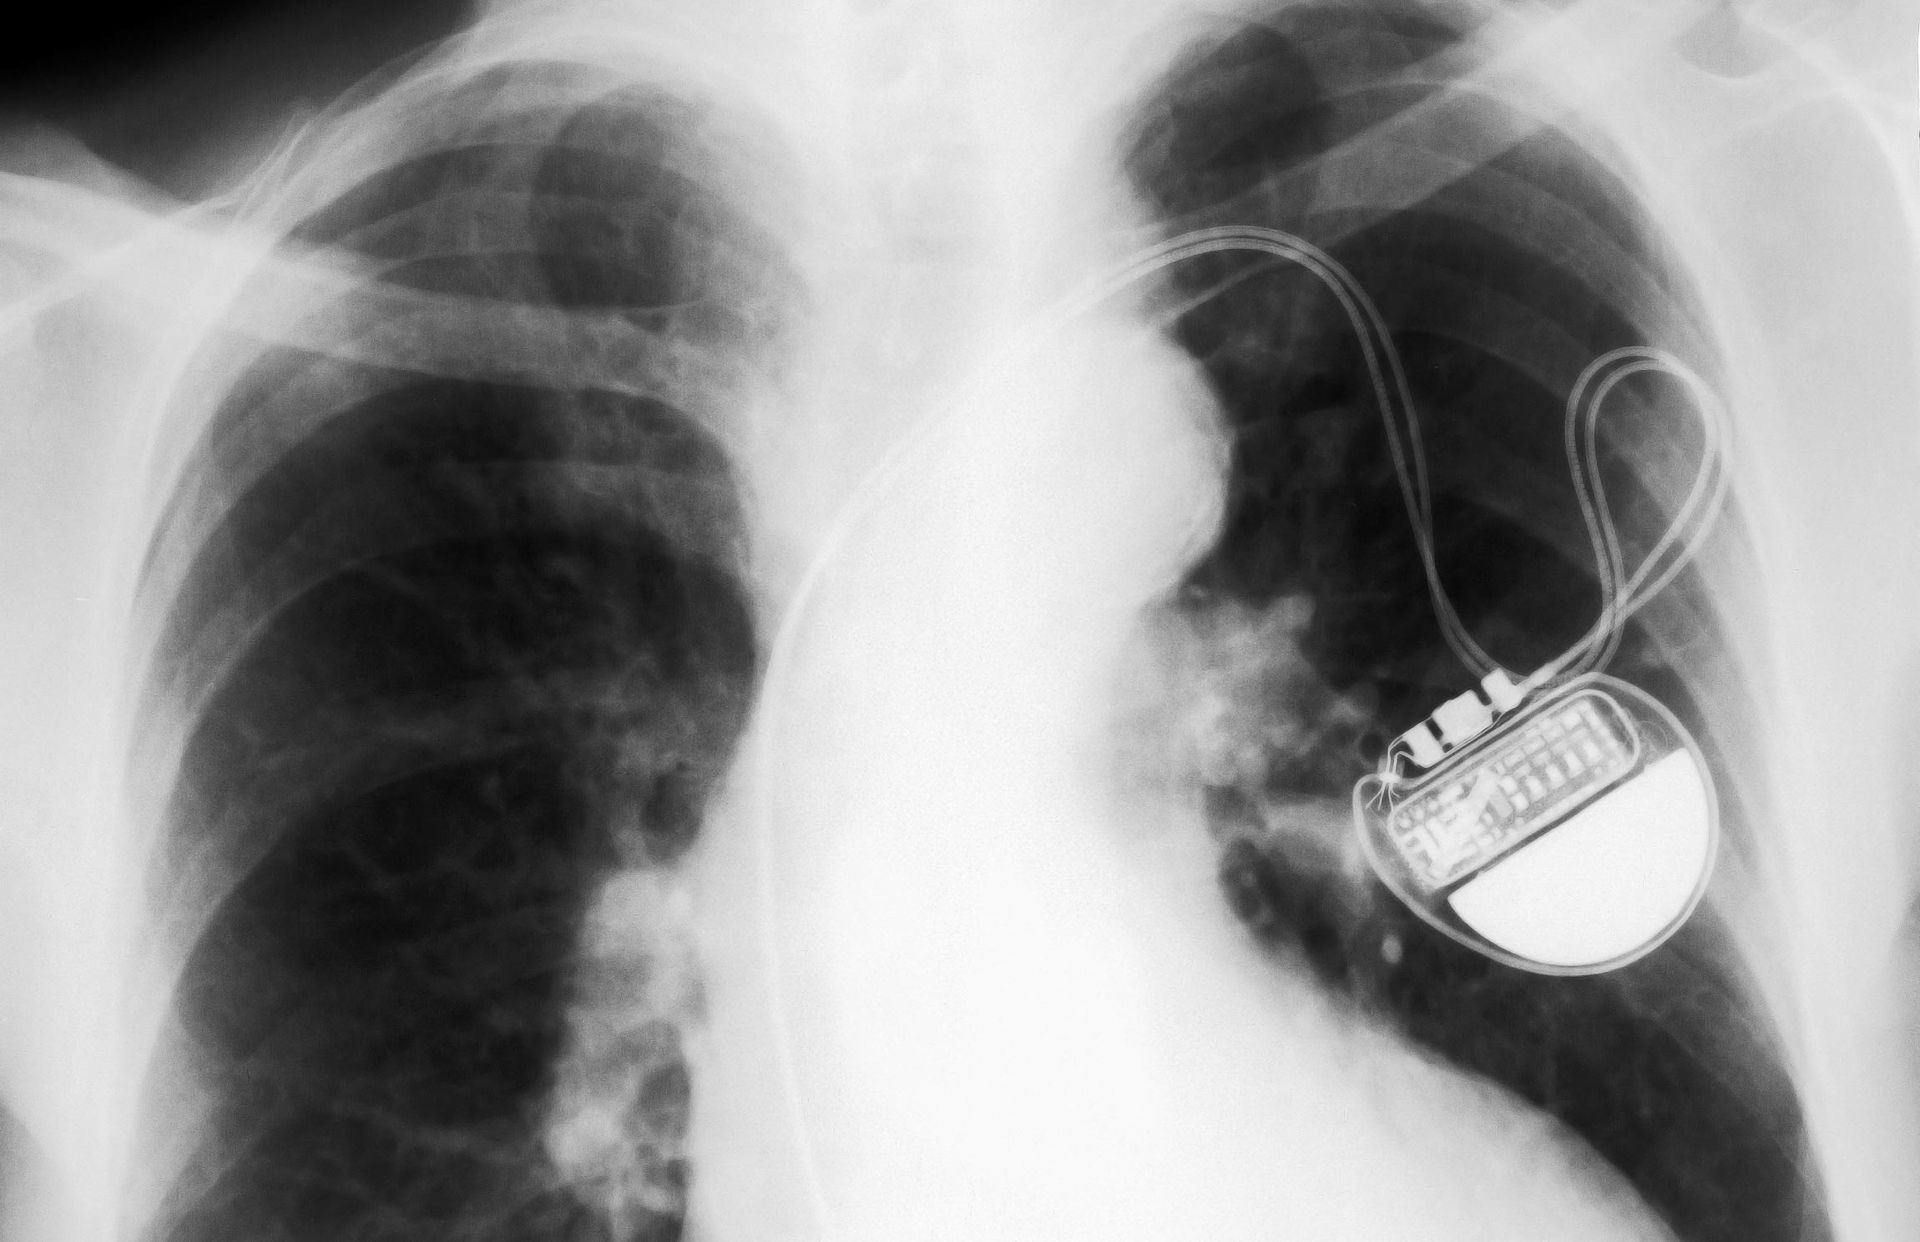

Es un dispositivo que se implanta quirúrgicamente en el pecho del paciente para ayudar a controlar los latidos cuando estos son muy lentos.

Marcapasos de cámara individual: se encarga de transportar impulsos eléctricos al ventrículo derecho del corazón.

Marcapasos de doble cámara: transporta impulsos eléctricos al ventrículo derecho y a la aurícula derecha del corazón para que controle el tiempo de las contracciones de ambas cámaras.

Marcapasos biventricular. Este tipo de marcapasos está especialmente dirigido a pacientes que sufren de insuficiencia cardíaca. Se encarga de estimular os ventrículos derecho e izquierdo del corazón.